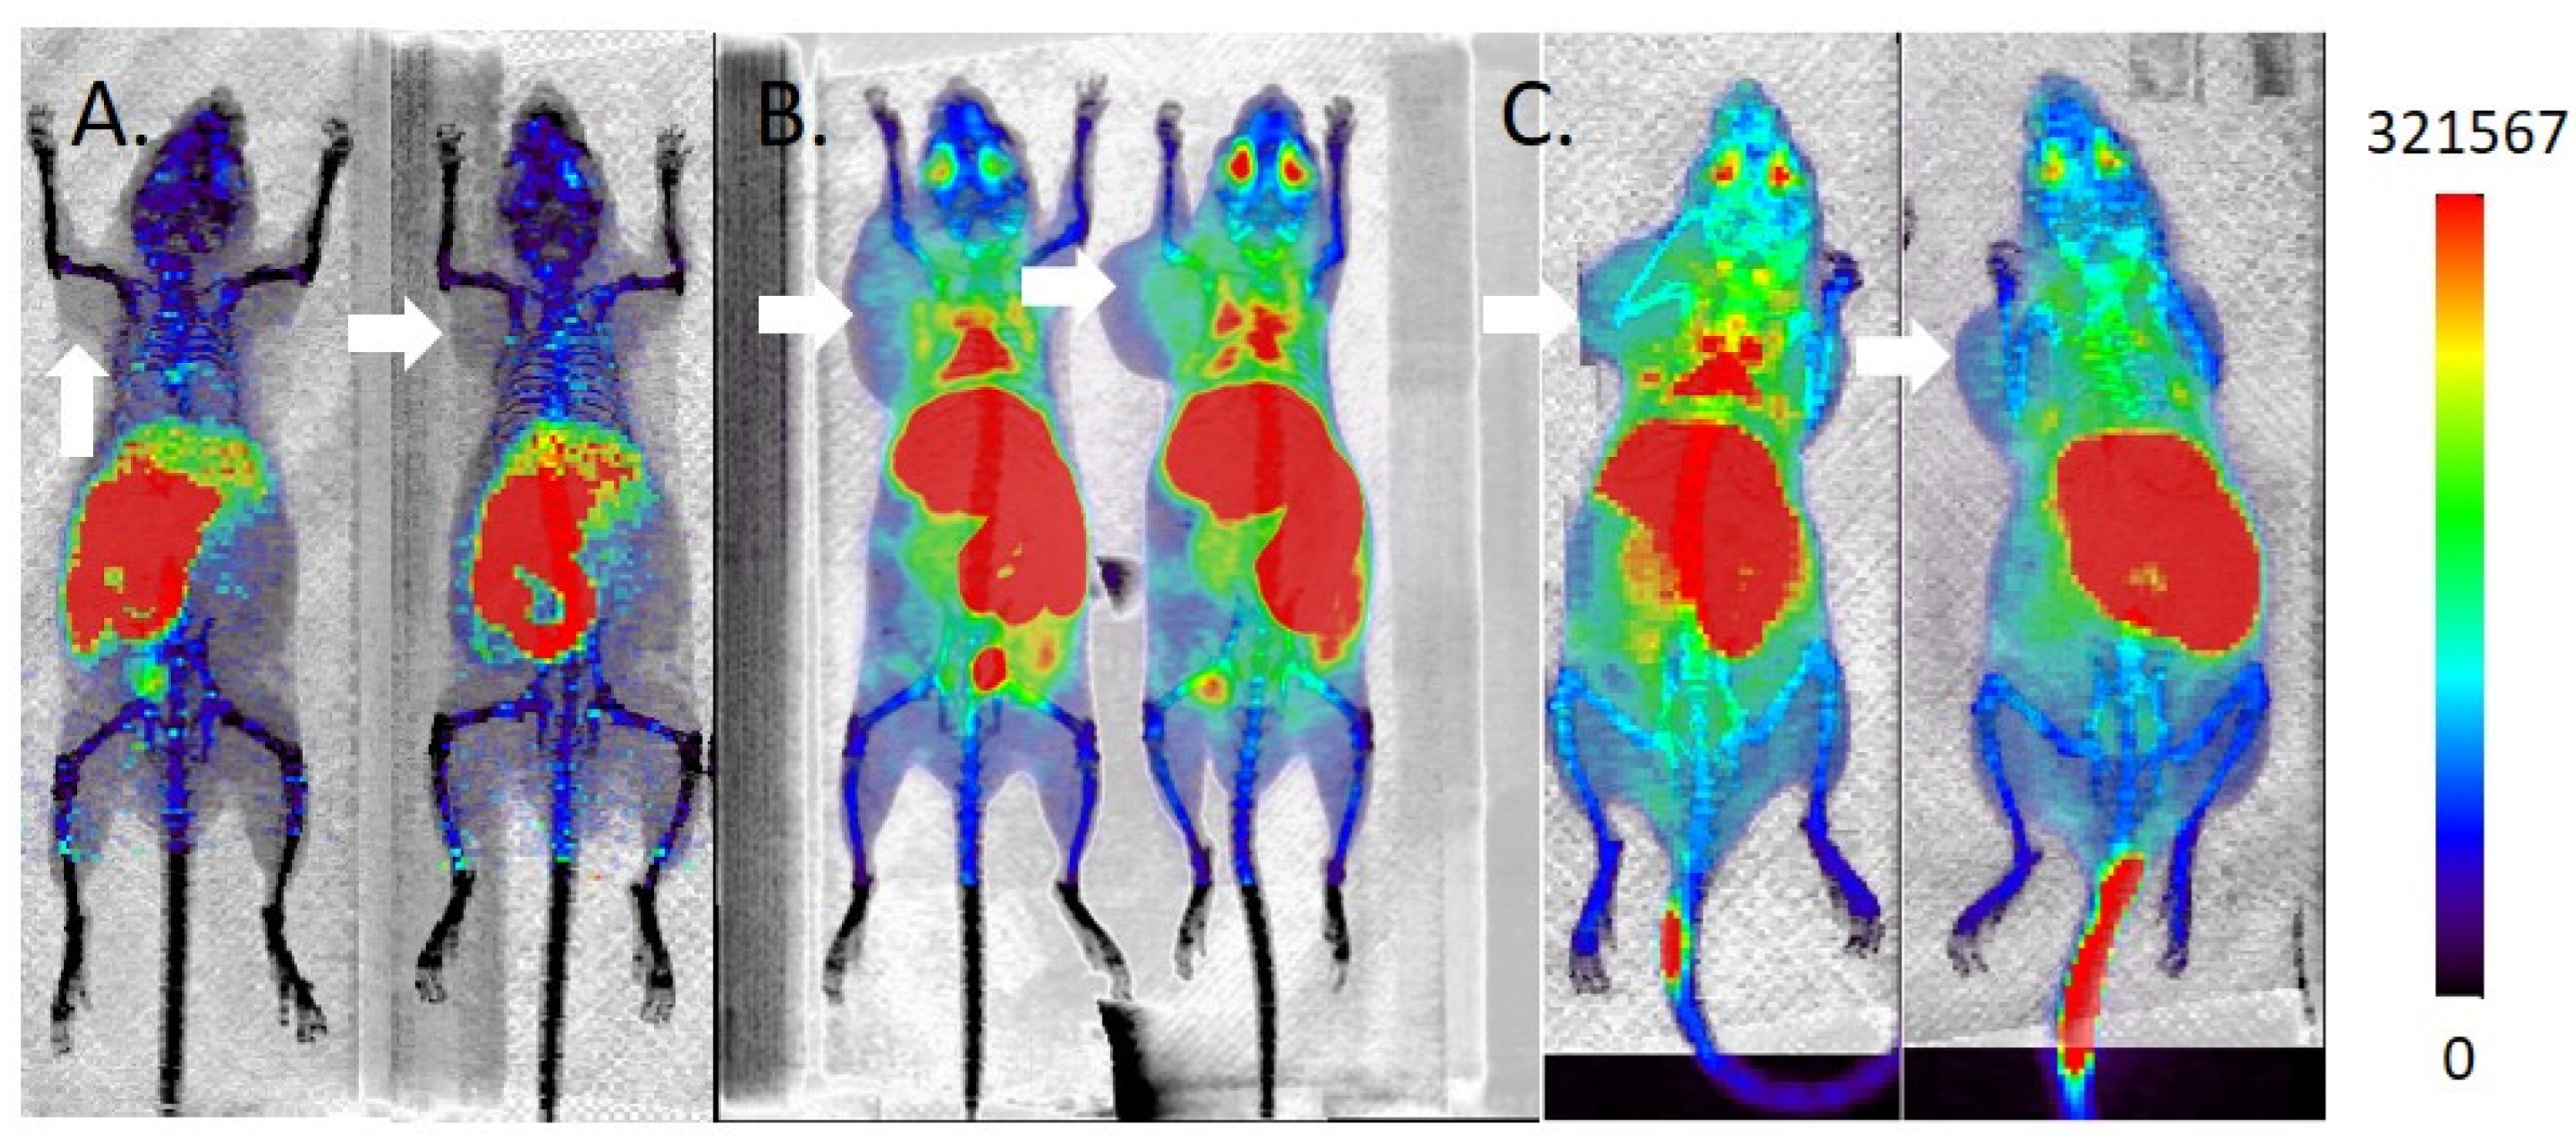

2.5. MicroPET/CT Imaging